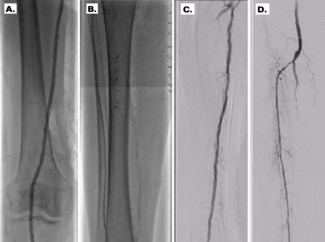

Patients with end-stage foot are commonly diabetic and/or have advanced chronic kidney disease. These patients are at very high risk for major amputation and generally are poor candidates for surgical revascularization due to poor target...